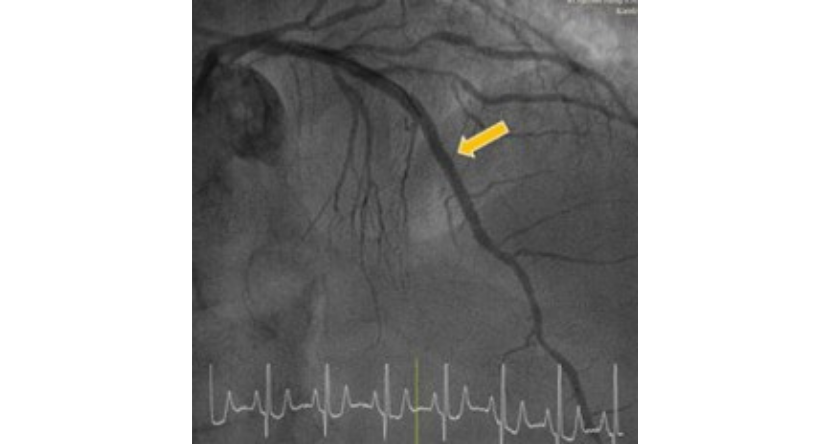

Balon dilatasyonu ve stent implantasyonu

En etkili yöntem, tıkalı koroner arterin balon dilatasyonu ve stent implantasyonu ile koroner anjiyografidir.Acil kalp kateterizasyonu (koroner anjiyografi) sırasında, tıkalı koroner arter ince bir tel ile incelenir ve ardından balon dilatasyonu ve stent implantasyonu ile tekrar açılır. Bu, kalp kasının etkilenen bölgesine kan akışını geri kazandırır ve iyileşme sürecini başlatır.